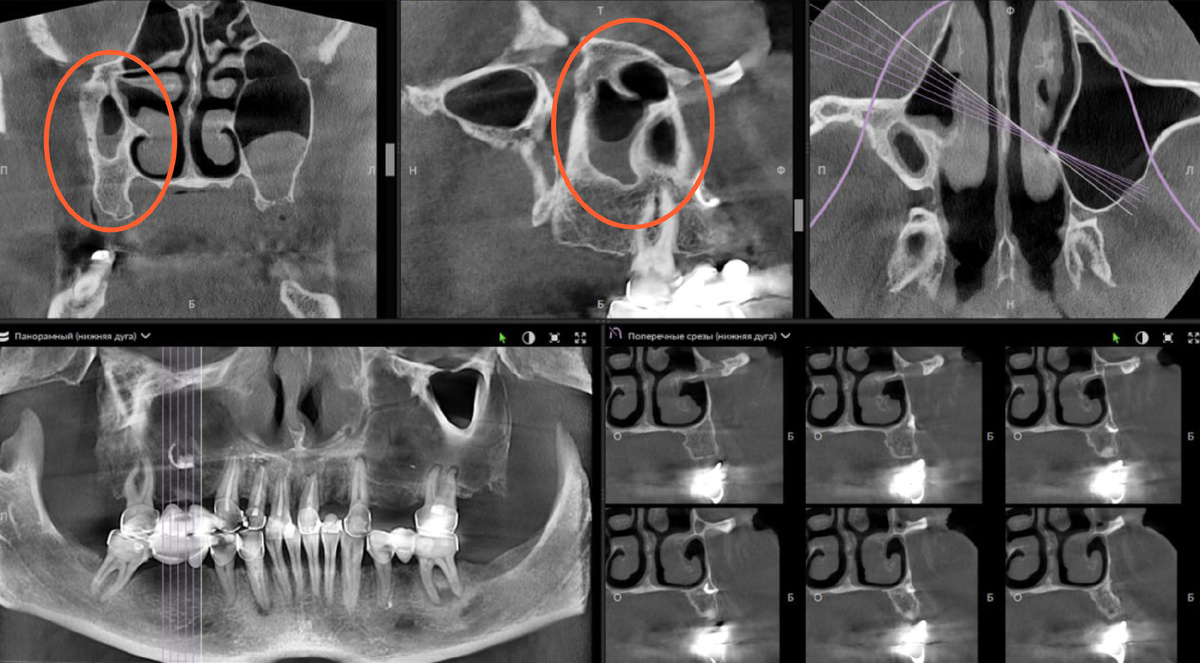

Гипоплазия правого максиллярного синуса. Случайная находка

Данный клинический случай предоставлен опытным врачом-рентгенологом Александром Потаповым👨‍⚕ Гипоплазия правого максиллярного синуса - уменьшение объема (просвета) синуса, уменьшение расстояния между костными стенками. Чаще всего гипоплазия - случайная находка при проведении рентгенологического обследования челюстно-лицевой области. В большинстве случаев течение асимптоматично и не требует вмешательств. На скриншоте панорамного реформата отмечается отсутствие воздушной полости из-за локализации уменьшенной пазухи вне выделенного слоя реформата. Поделитесь в комментариях, с какими случайными находками вы сталкивались в своей практике при проведении рентгенологического обследования пациентов 💻 Узнайте подробнее о программном обеспечении DTX Studio Clinic, оставив заявку на консультацию. ________________

Гипоплазия правого максиллярного синуса - уменьшение объема (просвета) синуса, уменьшение расстояния между костными стенками.

Чаще всего гипоплазия - случайная находка при проведении рентгенологического обследования челюстно-лицевой области.

В большинстве случаев течение асимптоматично и не требует вмешательств.

На скриншоте панорамного реформата отмечается отсутствие воздушной полости из-за локализации уменьшенной пазухи вне выделенного слоя реформата.